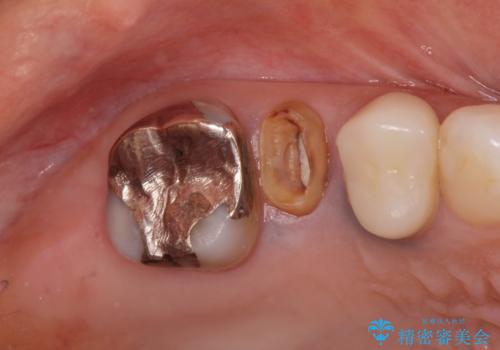

- 「奥歯のクラウンが取れてしまったので診てほしい。」とセラミック治療を希望され来院されました。

診査を行ったところ、クラウンの取れた歯は、割れてしまっており再度クラウン装着が難しい状況でした。

抜歯を行ったのち、ブリッジ製作を行うことで咬合機能の回復を計画します。